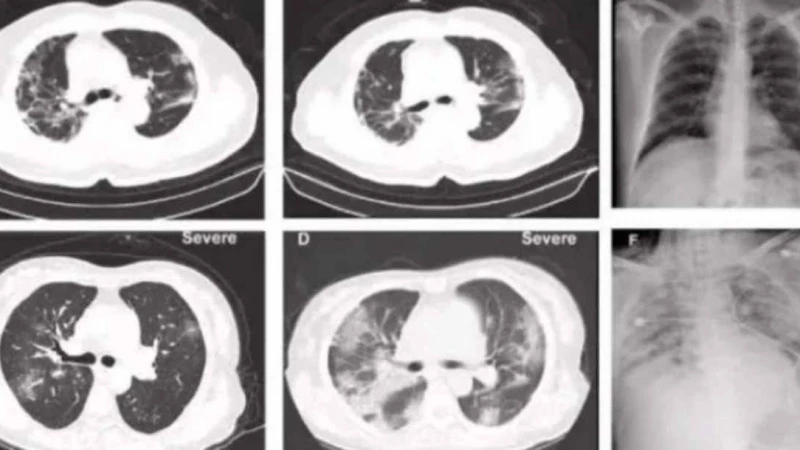

Ауруханаға жеткізілгенде науқастың қызу, жөтел және басқа да вирус белгілері байқалмаған. Ауруханаға түскеннен кейінгі 10- күні науқастың тамағында қышу пайда болып қызуы көтерілген. Компьютерлік томографиядан оны4 екі өкпеcінде инфекция бар екені көрінді.

20-күні өкпеге жасалған томографияда инфекция одан әрі таралып жатқаны көрінген. 28-ші күні науқас көз жұмып, оған «коронавирустың жаңа түрінен туындаған пневмония, тыныс алу жеткіліксіздігі» деген диагноз қойылған.

«Зерттеу нәтижелері көрсеткендей,  бұл тыныс алу жолдарының және өкпе альвеолаларының терең бөліктерінің зақымдануы, бұл коронавирустың жаңа түрінен туындаған пневмония. Марқұмнан ертерек алынған анализде COVID-2019 патологиялық процесі SARS-ке ( SARS - бұл жіті респираторлық синдром) және MERS-пен (Таяу Шығыс тыныс алу синдромы)өте ұқсас екенін көрсетті, алайда COVID-2019-да өкпе фиброзы SARS-қа қарағанда ауыр емес », - делінген хабарламада.

«Біз «дұшпанның» қай жерде екенін, оның «қаруы» не екенін, күшін білмейміз. Патологиялық анатомия мен кейінгі зерттеулердің арқасында вирустың адам ағзасына таралуын микроскоптың көмегімен байқауға болады. Қандай мүшелер, ұлпалар мен жасушалар ең көп зардап шеккенін, «жаудың» әлсіздігі не екенін түсінуге болады. Компьютерлік томографиясы науқастың өкпесінде өзгеріс белгілерінің пайда болуын көрсетті », - дейді дәрігер Лю Лян.